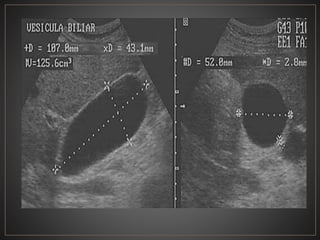

• #15 USG en escala de grises con transductor convexo en corte longitudinal y transversal, vesicula biliar se observa distendida, ecolucida, con medidas de 107x43x52 mm con un grosor de pared de 2.8 mm